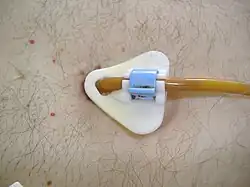

Physical therapy can promote functional independence[100][101] through aerobic, range of motion, and stretching exercises.[102] Occupational therapy can assist with activities of daily living through adaptive equipment.[103] Speech therapy can assist people with ALS who have difficulty speaking.[101] Preventing weight loss and malnutrition in people with ALS improves both survival and quality of life.[9] Initially, difficulty swallowing (dysphagia) can be managed by dietary changes and swallowing techniques. A feeding tube should be considered if someone with ALS loses 5% or more of their body weight or if they cannot safely swallow food and water.[10] The feeding tube is usually inserted by percutaneous endoscopic gastrostomy (PEG). There is weak evidence that PEG tubes improve survival.[104] PEG insertion is usually performed with the intent of improving quality of life.[17]

A feeding tube should be considered if someone with ALS loses 5% or more of their body weight or if they cannot safely swallow food and water.[10] This can take the form of a gastrostomy tube, in which a tube is placed through the wall of the abdomen into the stomach, or (less commonly) a nasogastric tube, in which a tube is placed through the nose and down the esophagus into the stomach.[16] A gastrostomy tube is more appropriate for long-term use[5] than a nasogastric tube, which is uncomfortable and can cause esophageal ulcers.[16] The feeding tube is usually inserted by a percutaneous endoscopic gastrostomy procedure (PEG). While there is weak evidence that PEG tubes improve survival in people with ALS, no randomized controlled trials (RCTs) have yet been conducted to indicate whether enteral tube feeding has benefits compared to continuation of feeding by mouth.[104] Nevertheless, PEG tubes are still offered with the intent of improving the person's quality of life[17] by sustaining nutrition, hydration status, and medication intake.[5]